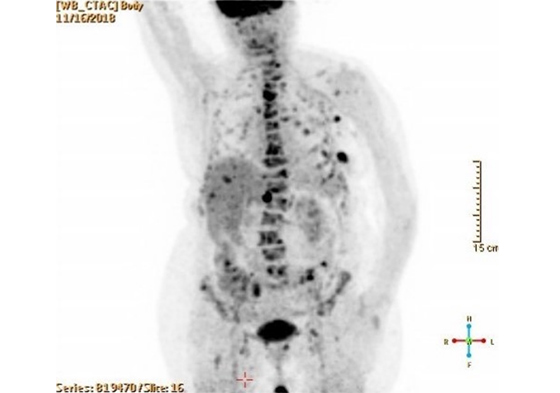

Этот цикл я писал, всматриваясь в медицинские снимки умирающего родного тела. Я пытался разглядеть его изнутри и осознать неосознаваемое: как это — постепенно умирать? Как отпустить, чем отстоять и куда его уложить, чтобы не было больно? В ужасе я наблюдал за расплывающимися узорами смерти, пока она не залила все живые уголки дряхлого тела. Снимки и тексты — свидетельства скрытого, немого страдания, которому я даю право быть увиденным и услышанным.

Это — кадиш по моей бабушке, которая умерла 18 января 2019 года. Была пятница, и похоронить ее нужно было до захода солнца — до начала Шаббата, который наступает в пятничный вечер. Кладбище было напротив больницы, через дорогу. Мы хоронили ее через три часа после смерти, не успев позвать ни родных, ни близких. Кадиш — это иудейская поминальная молитва. Для ее чтения необходим миньян — десять мужчин. Нас было меньше, поэтому хоронили без молитвы, спешно. Эти стихотворения — мой кадиш, который тогда мне произнести не дали, мое отпевание пустоты, что осталась после нее. В кадише использованы реальные медицинские материалы — рентгеновские снимки, УЗИ, КТ, ЭКГ — из истории болезни бабушки, с момента обнаружения рака и до самой смерти. Последняя кардиограмма была снята с мертвого тела. Так требовал больничный протокол.